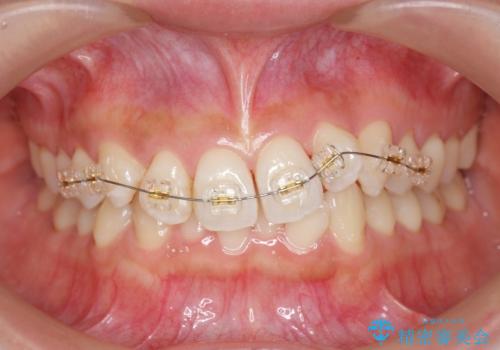

ワイヤー部分矯正治療を併用したマウスピース矯正治療

- 前歯のねじれ、深い噛み合わせ(ディープバイト)の改善を求めて来院されました。

マウスピースでは改善の難しい、歯のねじれ・ディープバイトを部分ワイヤー矯正で改善したのち、マウスピース矯正で全体の歯並びを整えていきます。

部分ワイヤー矯正を行ったことで前歯をしっかりと綺麗な歯並びへと導くことができました。